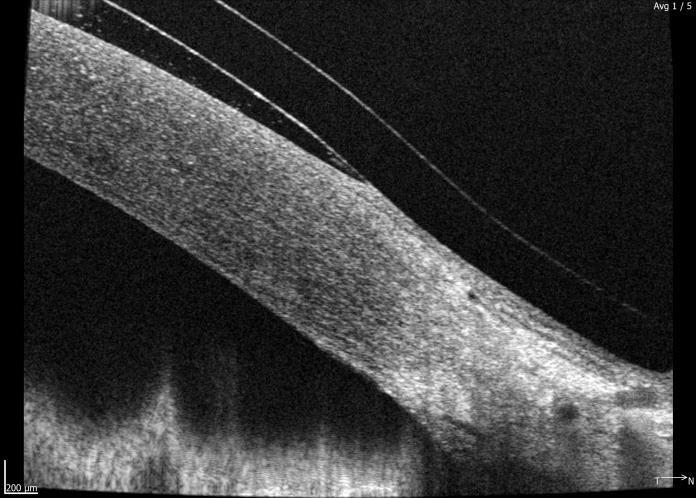

Initial maps were taken and used to design the lenses (Fig 1-3). At the patient’s aftercare appointment she was asked to wear the lenses for at least three hours (images of the lens on the eye and OCT scans are shown in Figs 4 to 7). OCT scanning is very useful in assessing post-wear fits as it allows for effective measurement of lens clearance at the apex and at the limbus, and for accurate assessment of the edge profile and its interaction with the sclera.

Fig 7. Anterior OCT scan after 3 hours of lens wear showing adequate medial limbal clearance and customised edge profile that follows the contours of the sclera